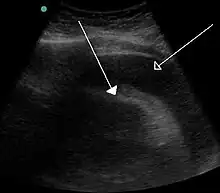

A very large hemorrhagic pericardial effusion due to malignancy as seen on ultrasound which was causing tamponade. closed arrow: the heart, open arrow: the effusion

Tamponade (/ˌtæm.pəˈnd/[1]) is the closure or blockage (as of a wound or body cavity) by or as if by a tampon, especially to stop bleeding.[2] Tamponade is a useful method of stopping a hemorrhage. This can be achieved by applying an absorbent dressing directly into a wound, thereby absorbing excess blood and creating a blockage, or by applying direct pressure with a hand or a tourniquet. There can, however, be serious consequences when a tamponade occurs as a result of health problems. For example: cardiac tamponade is a condition where fluid collects in the pericardial sac increasing pressure within the pericardium which in turn prevents the ventricles from expanding fully significantly reducing the efficiency of the heart. It is considered a medical emergency and if left unchecked is fatal.